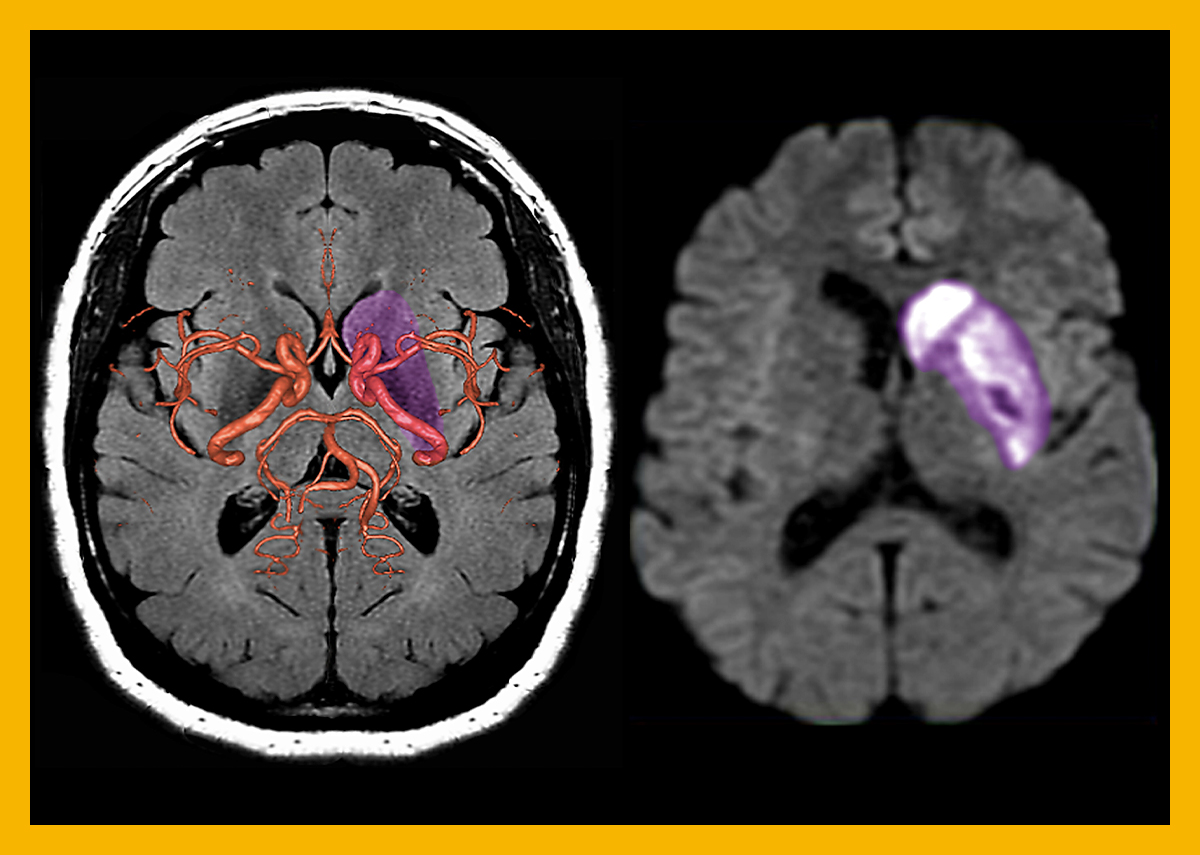

파킨슨 병이 진단 방법은 환자를 직접 보고 관찰 후 임상적인 진단을 하는 것이 대표적인 방법입니다. 하지만 꼭 MRI 찍어야 되는 경우도 있게 되는데요. 그 이유는 "비전형적인 파킨슨증"과 "수두증" 혹은 "2차적인 파킨슨증" 외 철분 침착과 같은 증상이 있는지 또는 뇌에서 특징적인 뇌 취축 증상이 있는지 확인하기 위함으로 MRI 찍는 경우도 있습니다.